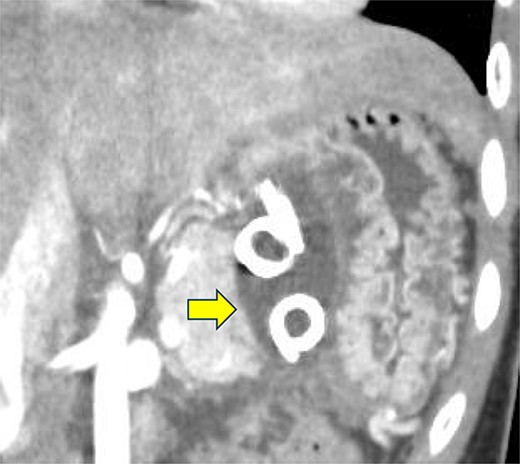

Contrast-enhanced CT on the 12th day. The pseudocyst in the omental bursa had shrunk. The arrow indicates the pseudocyst.